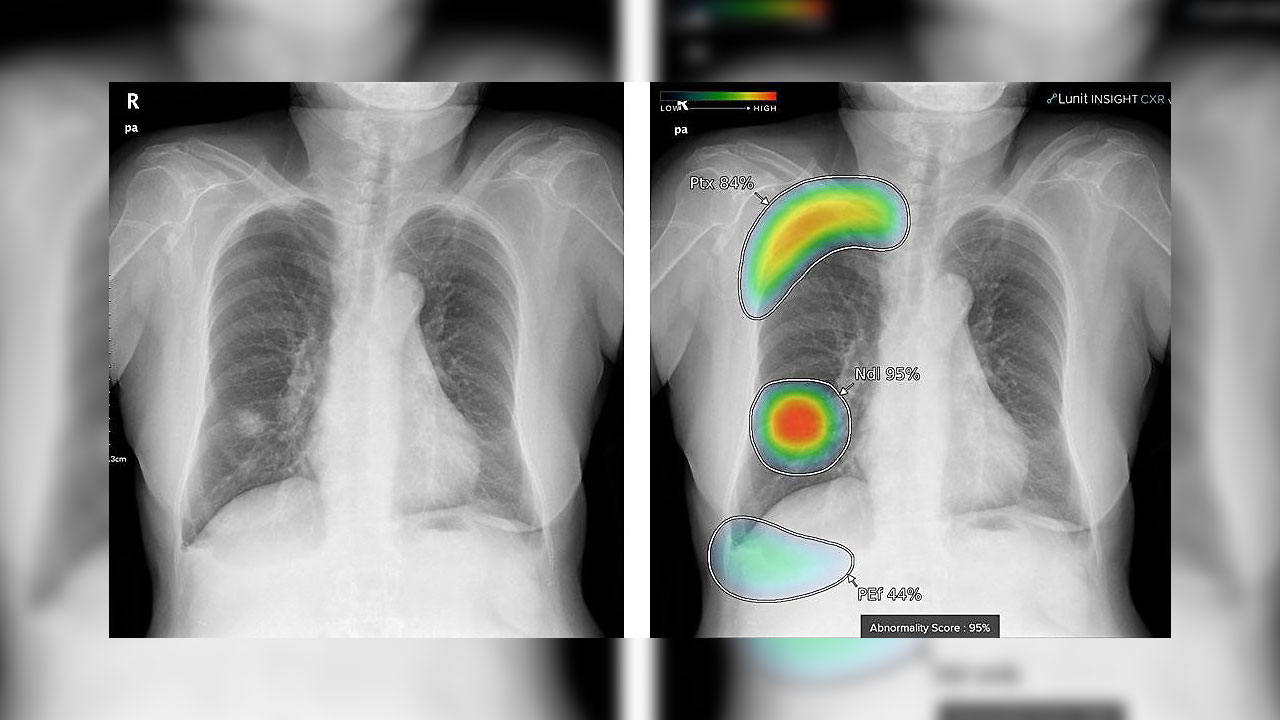

Сегодня мы говорим о том, что было бы неплохо иметь доступ ко всему багажу данных, смотреть динамику процессов, например, в легких, молочной железе, головном мозге. Это динамические параметры, их анализ требует большей квалификации, аналитических способностей. И человеку тут явно нужен помощник. Информационные технологии сегодня выходят на позицию такого ученика-помощника. Есть такой устоявшийся термин в английском — attendant. Именно технологии становятся помощниками врача при принятии решения. Они должны помогать не пропустить что-либо. Машина не подвержена усталости, машина не подвержена предвзятости — это отличные характеристики для помощника врача будущего».

Павел Румянцев: «Мы говорим о системах экспертной поддержки врачебных решений. Это значит, что врач, помимо собственного заключения, имеет поддержку всего мира доказательной медицины, мнения других экспертов, квалификация которых заключена в аналитических системах. Они должны подсказывать возможность других вариантов событий или природы процессов. Таким образом, расширяется поле дифференциальной диагностики. Мы уменьшаем количество неправдоподобных диагнозов, расширяем «поля зрения» диагностики. Время до диагноза сокращается, эффективность ранней диагностики повышается, доступность высококвалифицированных услуг растет. Качество услуг растет, потому что возникает и совершенствуется система внутренней валидации, аудита.

Технологии все глубже проникают в здравоохранение. Если говорить о центрах онкологической направленности, то тут важным этапом стал переход к использованию систем PACS для хранения графических данных, изображений. Используя такие данные, можно получить много важной информации по конкретным заболеваниям. Также на этих данных обучаются рекомендательные системы, помогающие врачам. Кроме того, уже есть возможность совмещать данные из разных исследований, визуализировать их, анализировать полную «картинку». Но далеко не все и не везде этим пользуются.

Павел Румянцев: «Технические возможности есть, но насколько широко это используется? Очень слабо, скорее какими-то отдельными группами для экспериментов или исследовательских целей. Дьявол – в деталях: нет готовых решений, когда «нажал на кнопку» и все готово. Решения надо создавать, визуализацию надо создавать. И производители медицинских систем в этом заинтересованы. Но тут движение должно быть со стороны медицинского сообщества. Сейчас из существующих возможностей технологий используется, наверное, меньше 1%. Нам нужно революционное развитие. Цифровая медицина невозможна без некоего большого скачка. Нужны прорывные проекты в онкологии, в кардиологи – везде, где это возможно. Методы визуализации сегодня лидируют по сравнению с остальными с точки зрения накопления данных, и нам нужно этим пользоваться.